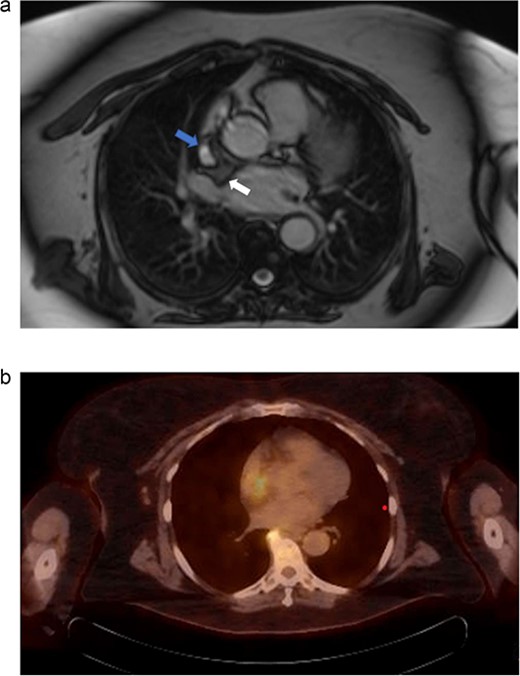

Electrocardiography revealed normal sinus rhythm. An echocardiogram was performed, which revealed a mass involving the interatrial septum extending superiorly toward the superior vena cava (Fig. 1). She had normal biventricular function with a left ventricular ejection fraction of 55%, no valvular abnormalities, and no evidence of obstruction. Subsequently, cardiac magnetic resonance imaging (MRI) was performed. This showed a 5.5 cm x 2.5 cm x 2.5 cm mass involving the interatrial septum with near encasement of the superior vena cava (Fig. 1). The mass extended inferiorly toward the inferior vena cava (IVC) and coronary sinus, but without obvious involvement. The mass was hyperintense on T1 and T2-weighted sequences. On T1 fat saturating images, it was hypointense. It showed contrast enhancement with gadolinium suggesting vascularity. The staging workup further included positron emission tomography (PET), which showed increased fluorodeoxyglucose-18 (FDG) uptake in the atrial tumor without evidence of extracardiac disease or metastases (Fig. 2b). These findings were suggestive of a primary cardiac liposarcoma. The patient was then referred to our clinic for consideration of resection. She was deemed an operable candidate and the tumor resectable.

(a) Cardiac MRI. Mass is represented by the arrow on the right. The left arrow demonstrates the SVC. (b) PET/CT. Uptake is demonstrated in the right atrium. Uptake near the spine was determined to be artifact and not representative of metastatic disease.